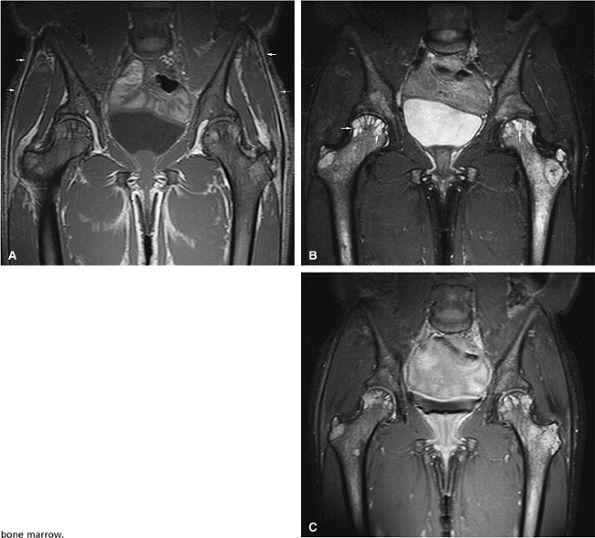

FIGURE 13.36 ● (A) An anteroposterior radiograph of the pelvis is negative for lymphomatous involvement. (B) On a T1-weighted coronal image of the pelvis, the proximal femurs and lower lumbar spine (arrows) display nonspecific low signal intensity. The fatty marrow of the epiphysis and greater trochanter is spared. (C) On a coronal STIR image, there is high-signal-intensity patchy nodularity of lymphomatous marrow involvement in the pelvis, proximal femurs, and lumbar spine (arrows). The spared yellow marrow of the greater trochanter and femoral epiphysis appears black.

Focal marrow lymphoma may simulate metastatic disease (Fig. 13.36). In contrast to Hodgkin disease, non-Hodgkin lymphoma demonstrates early bone marrow involvement.